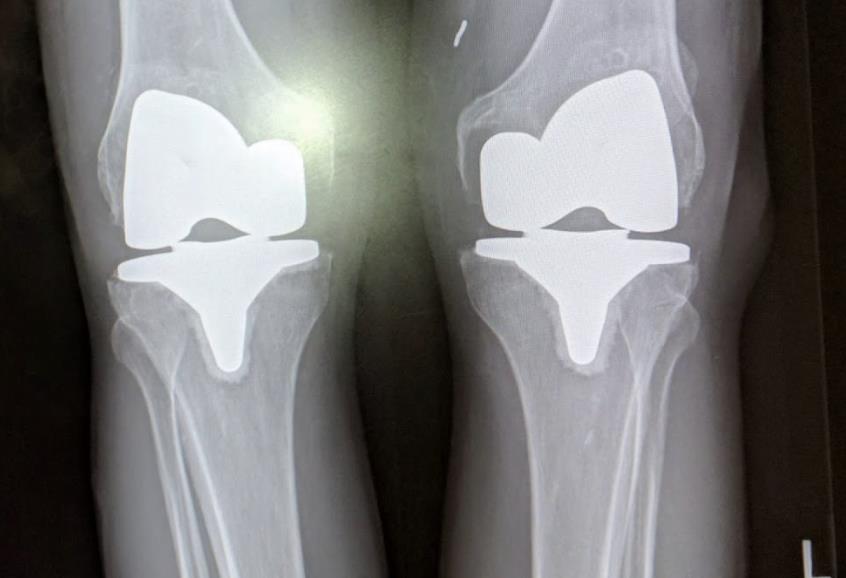

[Blocked from Release] ATTUNE™ Knee System

• The ATTUNE™ Primary Knee System is designed with the goal of addressing the clinical needs of patients, surgeons, and hospital providers around the world.

• Extensive research and science is included in the design to improve functional outcomes for patients1, performance for surgeons, and efficiency for providers.

• Candidates for total knee replacement include patients with a severely painful and/or severely disabled joint resulting from osteoarthritis, post-traumatic arthritis, rheumatoid arthritis, or a failed previous implant.